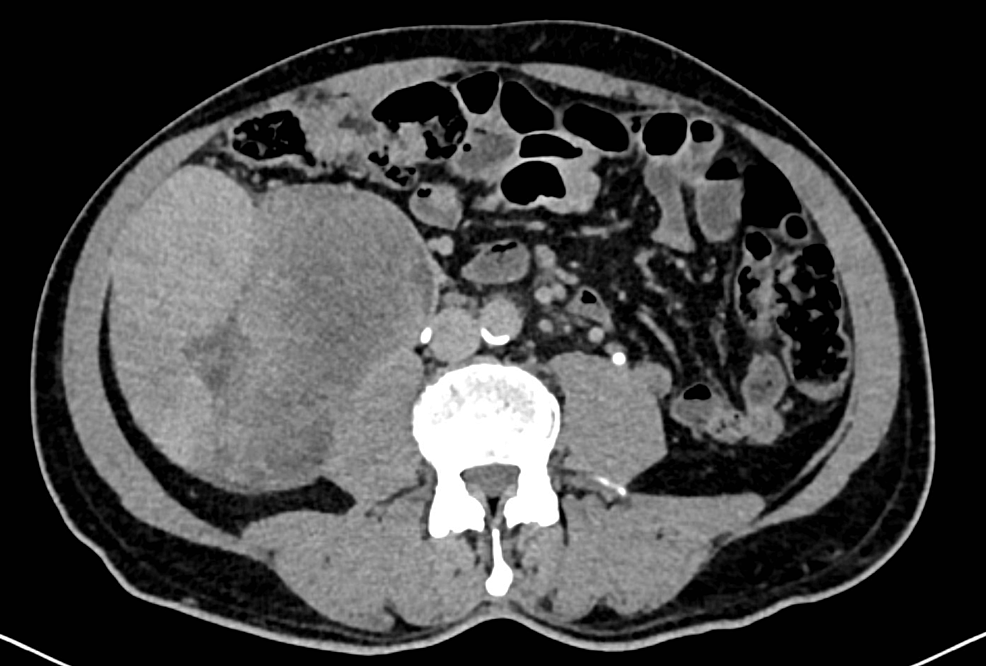

From www.researchgate.net

CT scan images showing the ureteric stump tumor Download Scientific What Is A Stump Tumor benign uterine leiomyomas, or smooth muscle tumors (smt), are neoplasms of the myometrial layer of the uterus and are the most common tumor in pelvic. the term smooth uterine muscle of uncertain malignant potential (stumps) indicates a group of uterine. a stump can be defined as a uterine smooth muscle cancer that cannot be diagnosed unequivocally as. What Is A Stump Tumor.

CT scan images showing the ureteric stump tumor Download Scientific What Is A Stump Tumor a stump can be defined as a uterine smooth muscle cancer that cannot be diagnosed unequivocally as benign or. benign uterine leiomyomas, or smooth muscle tumors (smt), are neoplasms of the myometrial layer of the uterus and are the most common tumor in pelvic. uterine stump is a rare neoplasm with heterogeneous histologic findings and diverse clinical. What Is A Stump Tumor.